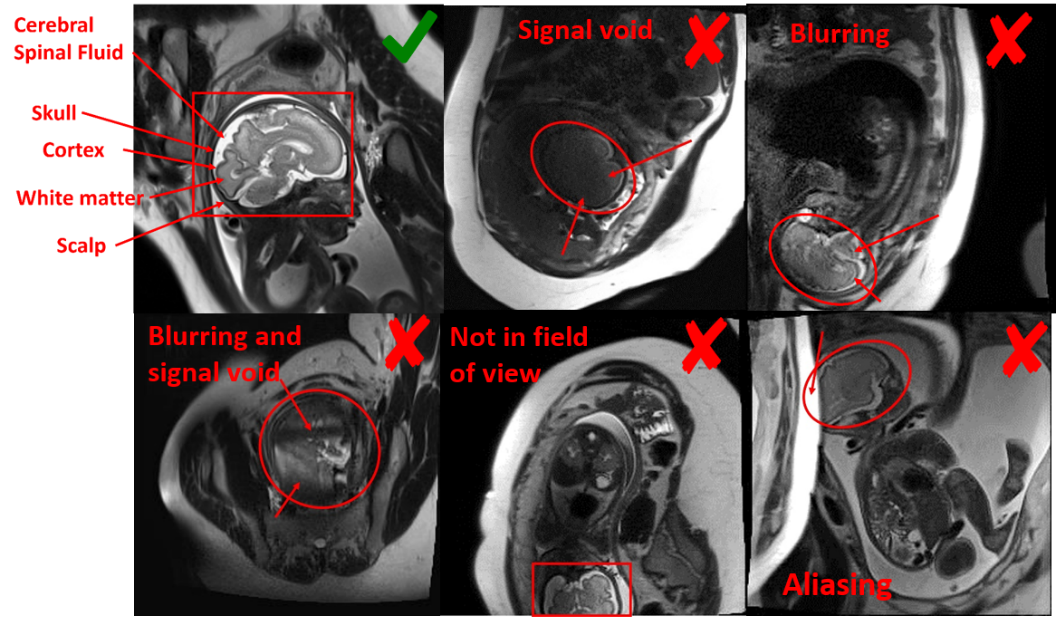

A set of 11223 images from 42 subjects are selected as labeled set and classified into three categories: diagnostic (D), non-diagnostic (N) and images without brain region of interest (W). Diagnostic images were characterized by sharp brain boundaries while non-diagnostic images were characterized by artifacts that occlude such features (Fig. 2). Motion artifacts manifest as signal void and blurring over the brain region. Other artifacts manifest as aliasing or the fetus not being in the field of view. A research assistant trained under radiologists labeled the dataset. The labeled dataset is divided into training (7717 images), validation (1782 images), and test (1724 images) set, where the test set consists of subjects different from training and validation sets.

Refer to caption

Figure 2: Representative examples of diagnostic and nondiagnostic quality fetal brain MRI